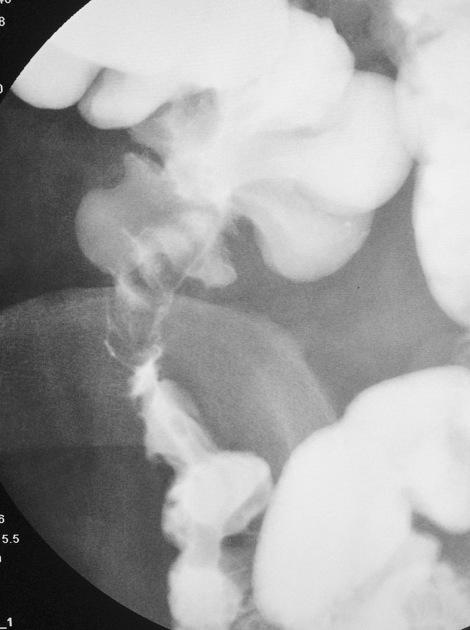

Image de lavement baryte en double de contrast :

Tuberculose ileo-caecale avec image de ileon tres

deforme , bord irregulier , angulation et stenosante

. |

Tuberculose ileo-caecale : image de

deformation en conique du caecum . Ileon est

irregulie et stenosante . Image de lavement baryte

mono de contrast . |